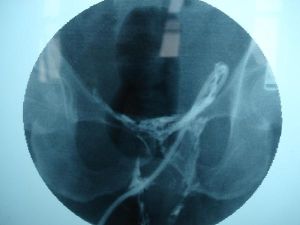

可在CT或B型超聲引導下細針穿刺抽膿,對吸出物做病理學、細菌學和生化檢查,並可將造影劑注入,測量膿腫大小,同時做置管引流,後者更能提高診斷及治療效果。